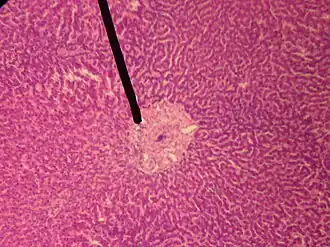

![]() A single lobule of the liver of a pig. X 60. (Central vein not labeled, though region is visible. Central vein would be a single vein at the center of the lobule.) | |

In microanatomy, the central vein of liver (or central venule)[1] is a vein at the center of each hepatic lobule.[2] It receives the blood mixed in the liver sinusoids to drain it into hepatic veins.[3]